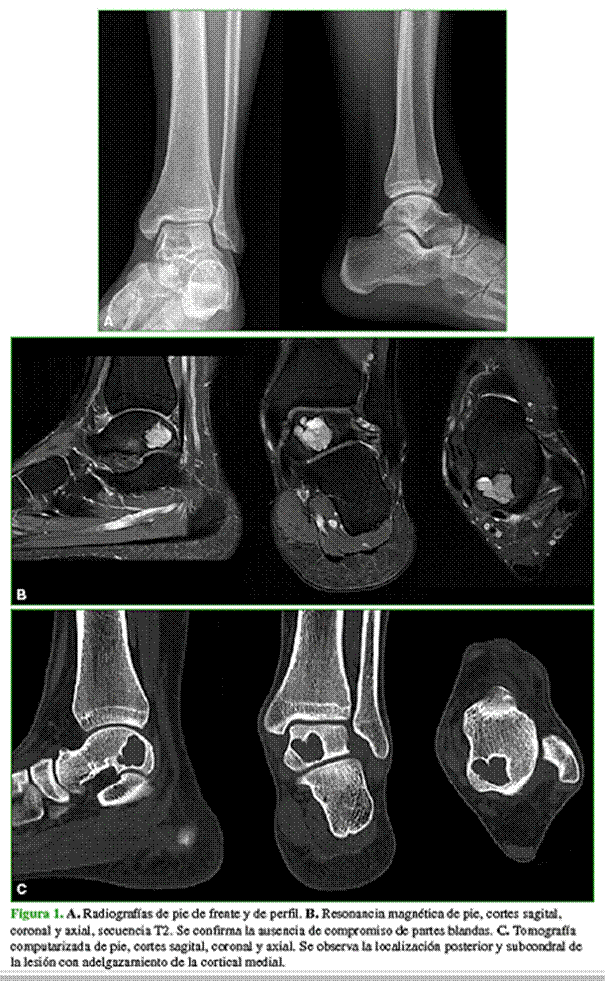

Varón de 18 años, sin antecedentes personales patológicos, que consultó por dolor de tobillo izquierdo en el Servicio de Urgencias. El paciente refirió el antecedente de una entorsis sin tratamiento, dos meses antes de la consulta. Inicialmente había sido tratado con fisiokinesioterapia, sin respuesta favorable, por lo que fue derivado al consultorio del especialista. Cuando se lo evaluó en el Departamento de Pie, refirió un dolor de 6/10 en la escala analógica visual. En el examen físico, se detectó dolor lateral de tobillo (ligamento tibioperoneo anterior ++/+++, ligamento calcaneoperoneo +/+++, estable a las maniobras de estrés). La radiografía mostraba una lesión lítica posteromedial del astrágalo, sin fractura de corticales. La resonancia magnética sin contraste y la tomografía computarizada revelaron una formación poliquística de bordes parcialmente escleróticos de 17 x 17 x 19 mm, con cortical superior e inferior del astrágalo adelgazada sin fractura evidente, algunos tabiques incompletos y sin calcificaciones (Figura 1).